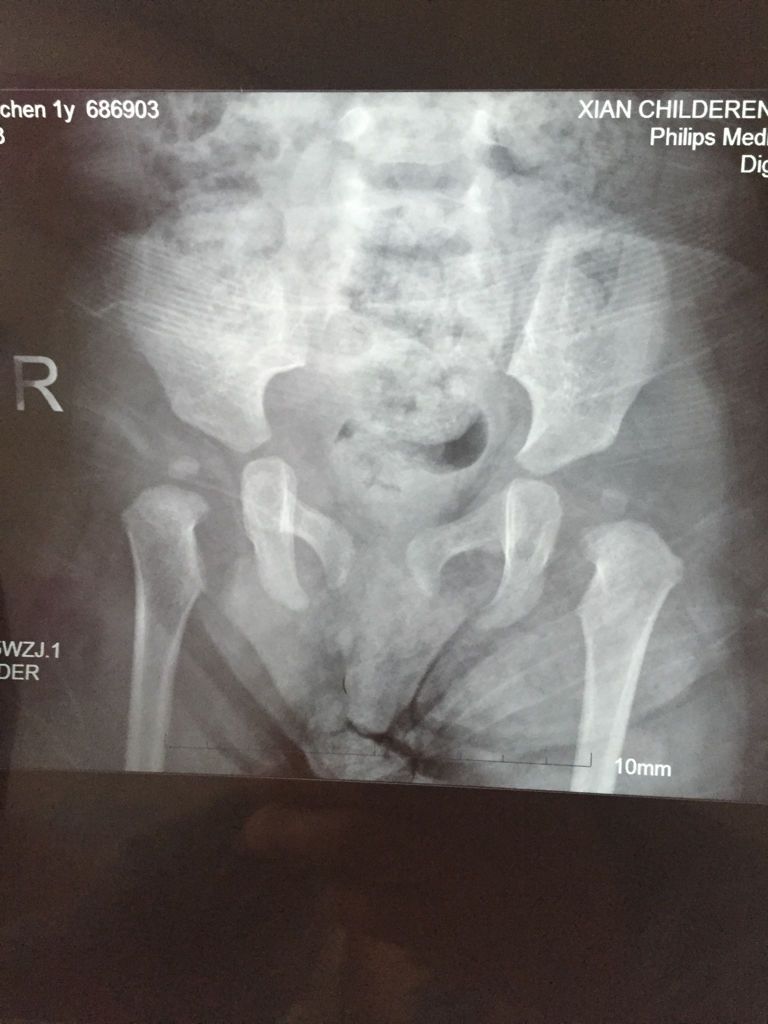

宝宝一岁四个月双侧股骨头骨骺化核较同龄儿小,尚位于髋臼内,双髋关节形态正常,关节间隙稍宽,医生说要 点击展开 匿名用户 2016-04-22 15:39 推荐回答 你好它残,这个保守治疗报葵套就能取得队亲较好效果的、。给你看一个患者的。, 匿名用户 2016-04-26 11:05 宝宝知道提示您:回答为网友贡献,仅供参考。 相关问题 宝宝3个月,腿纹不对称,双侧骨骺未出现,骨臼发育显浅平,髋臼角稍增大,关节间隙稍增宽,沈通氏线欠连续 男孩16岁,关节间隙存在,但骨骺已愈合,现在不到1米7,还能长吗 骨盆髋臼后壁骨折愈合后股骨头坏死几率大不